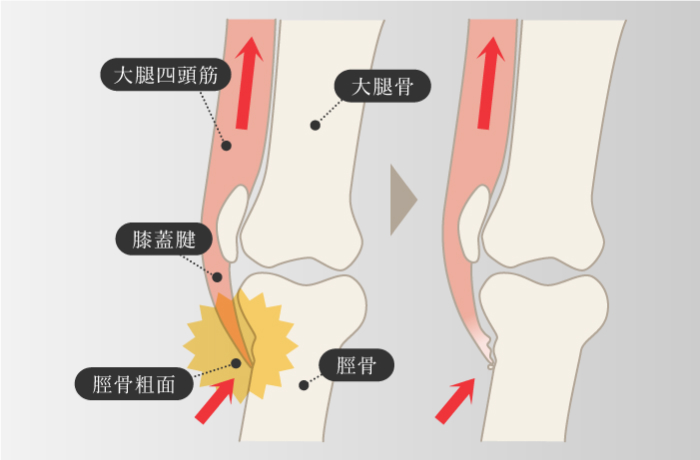

オスグッド・SLJ

-

成長期の子どもは、骨の成長に筋肉の成長が追いつかず、バランスがうまく取れていない場合があり、その状態では筋肉に強度と柔軟性がないので、スポーツなどの運動を過度に行なうと、大腿四頭筋が付着する脛骨粗面部に負荷がかかり、脛骨粗面部の隆起や炎症、痛みが生じる。